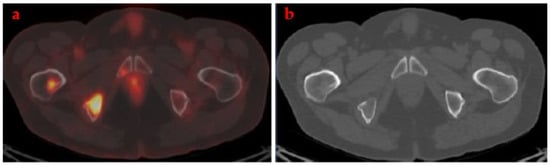

- FDG-PET/CT is recommended in the initial staging or re-staging, in oligometastatic disease staging when considering radical treatment. FDG-PET/CT is also recommended in patients with lymph node involvement outside the pelvis or in case of indeterminate/suspected metastatic lesions in high risk patients.

- Rescue treatment with curative intent could be considered in patients with oligometastatic disease after complete response on FDG-PET/CT.